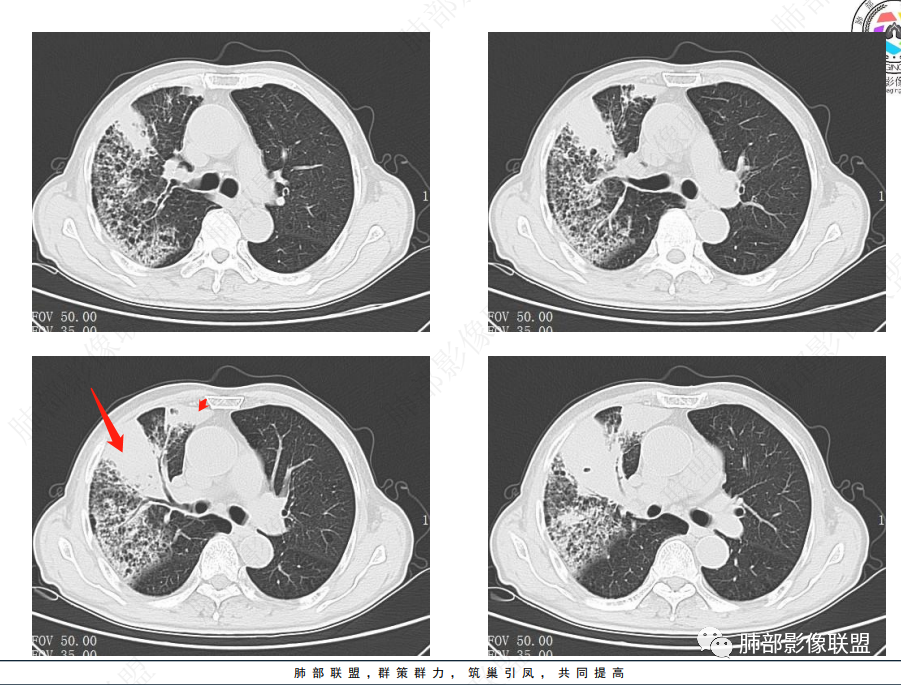

晨读病例,老年男性,乏力,纳差,近来发热,右肺上叶团片状阴影,内见空洞,空洞内壁不光滑,见短液平,增强病灶壁可见不均匀强化,似有边界不清晰的坏死,病灶周围可见片状模糊阴影,考虑恶性病变,鳞癌或腺癌伴感染。

老年男性,肺气肿背景,右肺较大分叶状肿块,密度不均,内坏死空洞形成,坏死区边界不规则,周围多发斑片蜂窝状、网格状高密度影,考虑鳞癌合并感染

右肺上叶及中叶不规则肿块伴周围模糊影,其内小叶间质结节样改变,肿块不均匀强化,坏死及空洞,坏死边界不清,血管显示尚可,考虑腺癌,鉴别淋巴瘤

老年男性,有咳嗽发热。右肺中上叶团状软组织肿块,周围磨玻璃渗出改变,病灶内密度不均,可见低密度坏死及空洞影,空洞内壁凹凸不平,近肺门侧可见明显大面积坏死。近端支气管堵塞不明显。考虑恶性肿瘤伴感染,腺癌?鉴别鳞癌,感染性病变。

右肺上叶团片状阴影,内见空洞,空洞内壁不光滑,偏心,,增强不均匀强化,内有边界不清晰的坏死,病灶周围可见片状模糊阴影,右下肺也有磨玻璃病灶,Crp高,腺癌

70岁男性,发烧病史,右肺巨大肿块,边缘分叶,内部空洞,洞内见附壁结节,局部支气管阻塞,肿块周围见大片阻塞性炎症;实验室检查,炎性指标增高;考虑恶性肿瘤伴阻塞性肺炎,鳞癌可能。

老年男性,乏力,纳差,发热。右肺上叶团片状阴影,密度不均,可见低密度坏死,坏死边界不清,可见空洞形成,见短液平;增强病灶呈不均匀强化,其内血管边缘模糊毛糙;病灶周围可见斑片状渗出病灶,支气管未见明确阻塞。综上考虑肺癌伴感染,鳞癌可能。

老年男性,纳差和发热,炎症指标明显。右肺磨玻璃影伴有肿块,肿块呈膨胀性生长,内部没有气管影。首先考虑感染,并有肿瘤的表现。考虑鳞癌合并感染

右肺上叶实变,密度不均,内可见小气液平,周磨玻璃影,斜裂稍内凹,右下肺可见斑片影,强化可见血管走行自如,右侧胸腔少量积液,考虑感染性病变,努卡?放线菌?

老年男性,肺气肿背景,右肺上叶及中叶大范围实变影,边界不清,支气管通畅,其内见边缘膨隆软组织块影伴不规则坏死、空洞,增强扫描不均匀强化,洞壁显示不清,血管稍变细,实变影内另见多发囊样影,右肺下叶小片状影,病灶跨叶,炎性指标增高,感染应该有的,不除外合并恶性肿瘤(鳞癌?腺癌?)

男,70,反复乏力、纳差20天,发热1天。胸部CT:肺气肿背景,右肺上叶中叶大团片影,实变十磨玻璃渗出。增强实性斑片影内密度不均,可见多发低密度坏死及不规则空洞影,空洞内壁尚光滑,血管边缘模糊。支气管管壁增厚,管腔通畅。右下叶可见小片渗出影。考虑支气管肺炎进展?病原考虑能形成肉芽肿、坏死空洞的微生物,TB?奴卡?鉴别鳞癌。

老年男性,乏力纳差,进食量明显下降,发热,后期少许黄脓痰,无咯血。无胸痛。未提口腔卫生情况,发热时间段不明确,肺气肿背景,气管内痰拴还是其他?觉得是外朝内进展病灶,右肺多叶段病灶,支气管通畅,支气管壁弥漫增厚,实变病灶内有坏死,坏死边界比较清晰,血管破坏不明显,周围散在磨玻璃,边界模糊,无树芽,实变内可疑小钙化,右侧胸水,肺门纵隔淋巴结无明显肿大。病史不太支持化脓菌感染,真菌里隐球强化不太支持,结核需要排除,厌氧菌感染带排,冠状位矢状位病灶觉得类圆形,临床肿瘤也是不能轻易排除的